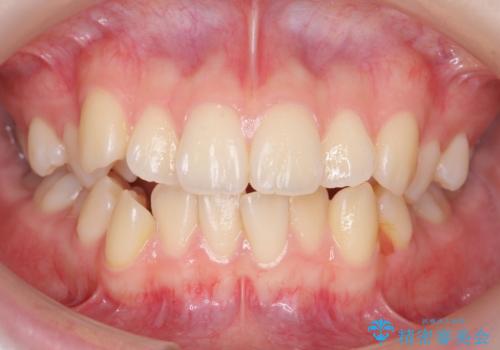

下の八重歯 歯を抜かずに インビザライン治療

- 歯並びのがたつきを主訴に来院。

抜歯してワイヤー矯正という選択肢も提案しましたが、マウスピース矯正で、歯を抜かずに並べてほしいとのことでした。

スペースを確保するために、歯をわずかに削る処置、奥歯を後ろに下げる処置(インプラント矯正)を行っています。